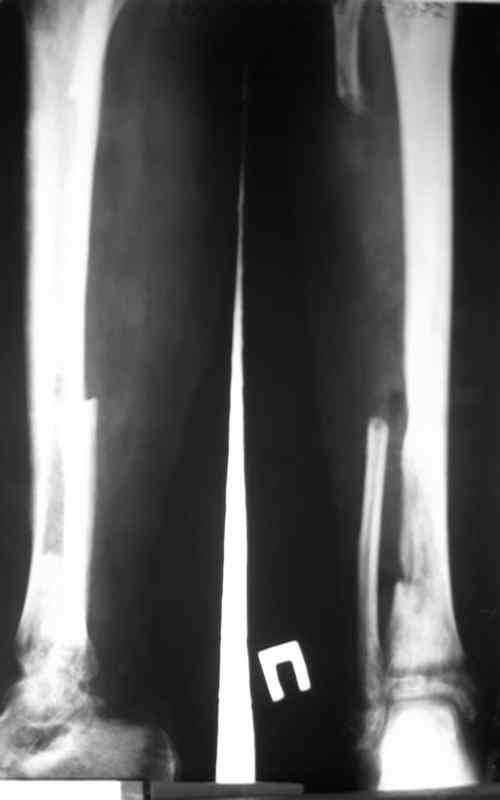

Доброго времени суток, коллеги! Сегодня поступил больной с остеомиелитом голени, 29 лет. Травма - январь 2007 года, <Открытый перелом малоберцевой кости,с повреждением малоберцевого нерва>. Первичных снимков нет. лечился в одной из районных больниц xUSSR. Обратился ко мне в сентябре 2007 года, сжалобами на наличие свищей,неопорность конечности.Был направлен после выполнения фистулографии (см. фото) в областной центр по лечению остеомиелита. Там была выполнено 2 операции: резекция малоберцевой кости, и повторный дебридмент. Последнее вмешательство около месяца назад. Послеоперационные снимки на фото. В течении месяца получал перевязки, и иньекции Бициллина- 5.Выписки больной не предоставил, вся информация с его слов. Опять же с его слов были рекомендованы перевязки с раствором димексида. На момент поступления раны и свищи хорошо видно на картинке, в дне раны кость жёлтого цвета, из раны гнойное отделяемое, с прямо таки неприятным запахом. (посев возьму завтра, но скорее всего там будет синегнойная, MRSA ). Стопа в эквинусе, активных движений нет, конечность неопорна. В связи с тем, что больной лечился в вышестоящей больнице, прошу скорректировать план лечения. Мой план: выполнить полноценный дебридмент, лаваж, <бусы>, рану зашить с дренажами по Редону. При выявлении поражения большеберцевой кости более 2\3 диаметра сегментарная резекция с последующим замещением дефекта по Илизарову. Активная ЛФК для голеностопа.